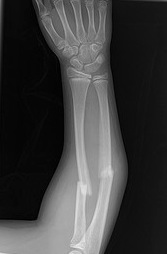

Hello Sensei Ando! Thanks for all your videos and articles. I started training kung-fu year and a half ago and unfortunately I broke my leg (tibia and fibula) while practicing sequence of kicks. I feel it was a pretty dumb accident and I hope to heal fast (ended up with a titanium rod). I am 41 years old, some friends who don’t enjoy martial arts look at me as if I am crazy to come back practicing. I really enjoy it. I think this accident could happen with any sport and that I need to be more mindful at class. This was a fast and powerful roundhouse kick to the air with improper pivoting and my back leg twisted and broke (so easy I was in shock). Now I will have more time to watch more videos! 😀 . You are a true motivator!